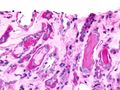

Micrograph showing myeloma cast nephropathy in a kidney biopsy. Hyaline casts are PAS positive (dark pink/red - right of image). Myelomatous casts are PAS negative (pale pink - left of image). PAS stain.

Histopathology